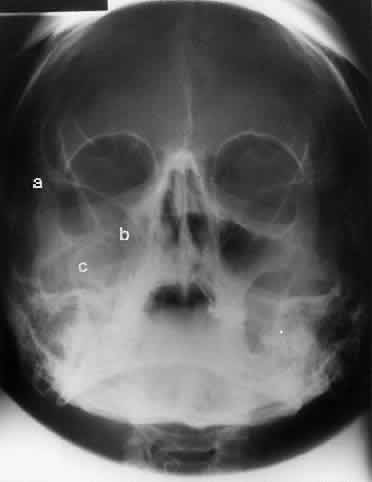

The optic foramen should measure 6 mm vertically and 5 mm horizontally. Asymmetry greater than 1 mm or a vertical dimension greater than 6.5 mm is considered abnormal.15,27 Ninety-eight percent of patients have optic canals that vary by less than 1 mm.27 Concentric enlargement of the foramen and optic canal can be seen with optic nerve gliomas, meningiomas, neurofibromatosis, and less commonly an aneurysm of the ophthalmic artery (Fig. 16). A decrease in the optic foramen and canal dimension can be seen in fibrous dysplasia, Paget's disease, hyperostosis secondary to a meningioma, or microphthalmos (Fig. 17, Table 1).

Fig. 17. Bilateral optic canal compression from fibrous dysplasia. There is diffuse bone thickening in each orbit. Note small size of optic foramen (arrow).